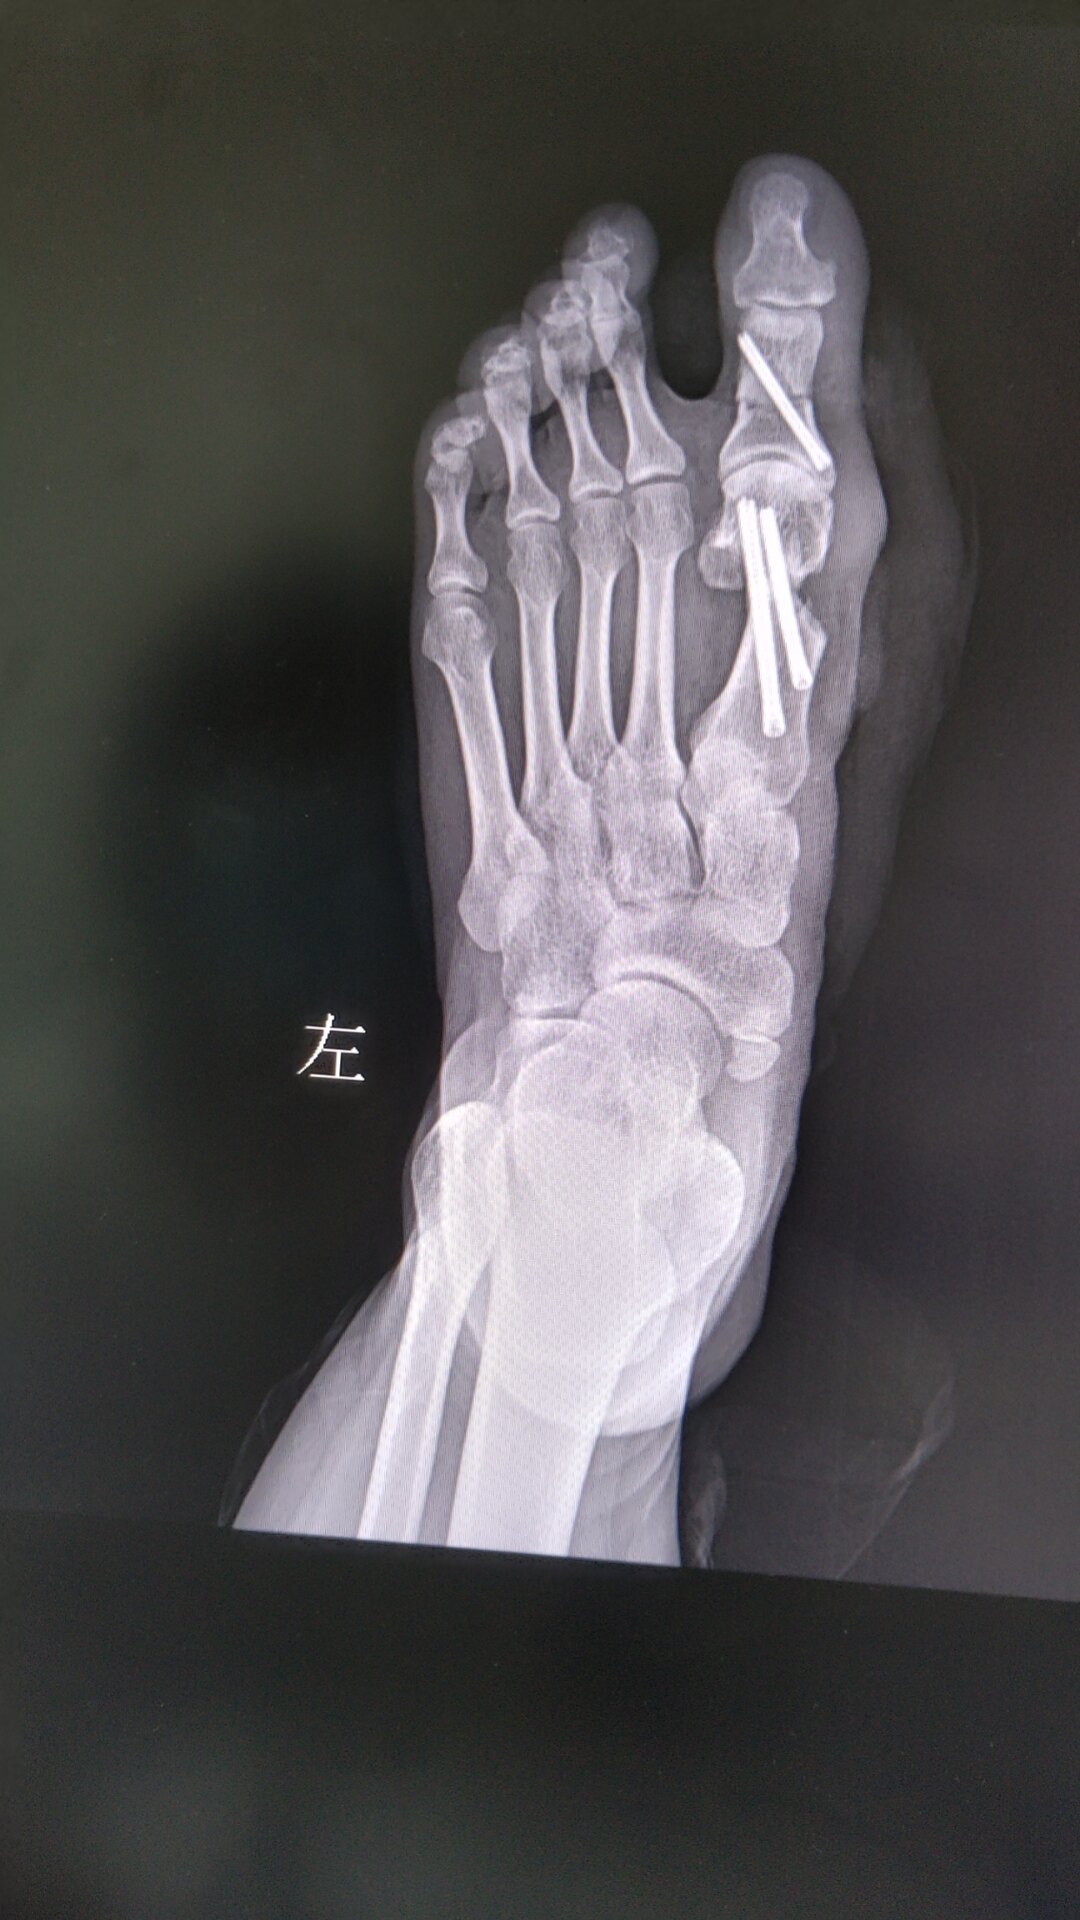

治療前患者34歲女性,雙足拇外翻,長(zhǎng)時(shí)間行走時(shí),雙足踇囊處出現(xiàn)疼痛,要求行微創(chuàng)治療。治療中選擇第三代微創(chuàng)技術(shù),兩枚螺釘固定,其中一枚選擇In-out~I(xiàn)n植入方式,固定可靠,早期即可負(fù)重活動(dòng)。治療后治療后即刻切口小,恢復(fù)快,局麻操作!

腳里要打釘子?談?wù)勧斪釉谀赐夥?chuàng)手術(shù)里起什么作用?

拇外翻的手術(shù)原理是通過(guò)手術(shù)操作,恢復(fù)拇趾第一跖趾關(guān)節(jié)內(nèi)側(cè)和外側(cè)關(guān)節(jié)的軟組織平衡。所有的拇外翻手術(shù)都需要從切口方式、截骨方式、固定方式、疼痛管理這四個(gè)方面考慮。切口方式主要分開放和微創(chuàng)兩種,切口的大小決定了術(shù)后的美觀程度和感染幾率的大小,開放手術(shù)中切口常規(guī)在5-8厘米,新MICA微創(chuàng)切口常規(guī)在0.3-0.5厘米。每個(gè)手術(shù)方式的截骨方式根據(jù)患者實(shí)際情況選擇也不一樣。開放手術(shù)開放手術(shù)截骨距離長(zhǎng),這個(gè)也就避免不了發(fā)生轉(zhuǎn)移性跖骨痛,愈合的周期相對(duì)較長(zhǎng),優(yōu)勢(shì)是手術(shù)時(shí)長(zhǎng)比其他方式要快。新MICA手術(shù)采用的是跖骨橫行截骨術(shù)+趾骨Akin截骨技術(shù),不會(huì)造成跖骨(大拇趾)縮短,可以避免導(dǎo)致轉(zhuǎn)移性跖痛的發(fā)生。截骨后必然有相應(yīng)的固定方式。每個(gè)醫(yī)生都會(huì)選擇自己常用的固定方式。我個(gè)人常用的新MICA微創(chuàng)手術(shù)采用的是空心螺釘固定,這是目前相對(duì)穩(wěn)定的方式,這種方法不僅使得第二天下地生活自理成為可能,還減少了住院天數(shù)和早期疼痛,方便外地患者就診;也減少了術(shù)后關(guān)節(jié)僵硬的風(fēng)險(xiǎn),可以避免矯形復(fù)位偏移,造成拇外翻復(fù)發(fā)。螺釘也影響著術(shù)后的疼痛管理。拇外翻手術(shù)的疼痛一般來(lái)自切口、斷骨兩個(gè)方面。由于新MICA手術(shù)的切口遠(yuǎn)遠(yuǎn)小于傳統(tǒng)開放手術(shù),切口的疼痛也會(huì)少很多。而新MICA手術(shù)里用來(lái)固定的螺釘,固定牢固,可以避免亂動(dòng)產(chǎn)生應(yīng)力疼痛,疼痛自然減少。螺釘還影響著術(shù)后護(hù)理與康復(fù),其穩(wěn)定的牢固性可以使足部達(dá)到一個(gè)穩(wěn)定的內(nèi)固定,方便術(shù)后進(jìn)行足趾的康復(fù)訓(xùn)練并早期下地活動(dòng)。這也是新MICA手術(shù)住院天數(shù)少、疼痛輕、術(shù)后第一天即可下床活動(dòng)的秘訣。